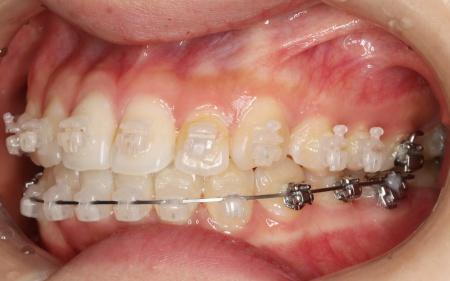

| 行った治療内容 | 患者様は「できるだけ目立たない治療方法で、なるべく早く終わらせたい」と希望されていたため、ハイブリッド矯正を提案し、同意いただきました。 ハイブリッド矯正とは、ワイヤー矯正とマウスピース矯正の両方を行う方法です。先にワイヤー矯正で歯を大きく移動させたあと、マウスピース矯正で仕上げることで、治療期間の短縮が望めます。 ただ2種類の矯正装置を使用するため、単独での矯正治療よりも費用が高くなる点がデメリットです。 ・ワイヤー矯正 歯の表面にブラケットと呼ばれるボタン状の装置を接着し、そこにワイヤーを通して歯を移動させる方法です。 患者様は目立たない治療方法を望まれていたため、ブラケットには白く目立ちにくい「セラミックブラケット」を選択しました。 ・マウスピース矯正 患者様専用のマウスピース(アライナー)を複数個作製して、定期的にご自身で交換しながら歯を移動させる方法です。 今回は、アライナーの枚数に制限がないプランである「インビザライン・コンプリヘンシブ」を選択しました。 まずは歯の表面にセラミックブラケットを装着し、ワイヤー矯正で歯を全体的に移動させます。 歯並びがある程度正しい位置に並んだら、マウスピース矯正で微調整を行いました。 歯の移動が完了したあとは定期的に経過を確認しながら、後戻りを防ぐためのリテーナー(保定装置)を継続して使用いただき、治療を終了しました。 |

治療中